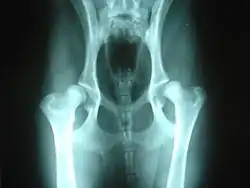

Klasický diagnostický postup využívá rentgenových snímků a bodovacího testu kyčlí. Provádí se v odpovídajícím věku a je vhodné ho zopakovat ještě v dospělosti (pokud se test udělá příliš brzy, jsou výsledky neprůkazné). Protože dysplazie je do velké míry dědičná, doporučuje se zkontrolovat stupeň dysplazie u rodičů před koupí štěněte a také při posuzování vhodnosti psa pro chov. Ale přestože je tato porucha dědičná, může se objevit i u psů, jejichž rodiče mají stupeň dysplazie negativní.

Existuje několik různých systémů pro posuzování stupně dysplazie, zpravidla však vedou k rozdělení do pěti kategorií: A – negativní, B – hraniční, C – mírná dysplazie, D – střední dysplazie, E – těžká dysplazie. Pro pořízení korektních snímků je nutná sedace zvířete, aby bylo možné ho udržet v klidu ve správné poloze a aby se snížil svalový tonus.